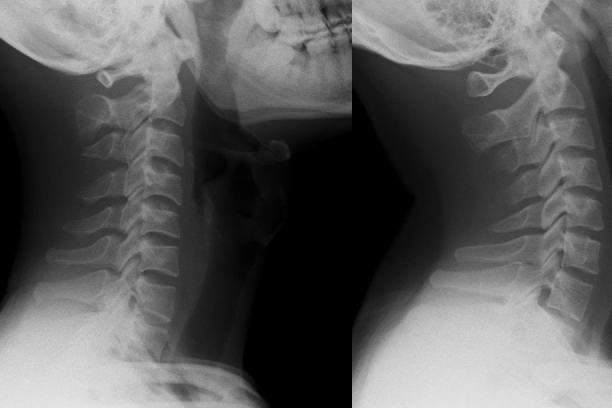

Nam thanh niên cột sống 'thẳng như cây gậy' vì thói quen triệu người mắc

Một nam nhân viên văn phòng 26 tuổi đã phải tìm đến bác sĩ vì tình trạng đau cổ vai gáy kéo dài. Kết quả chiếu chụp ghi nhận cột sống của bệnh nhân "thẳng như cây gậy".